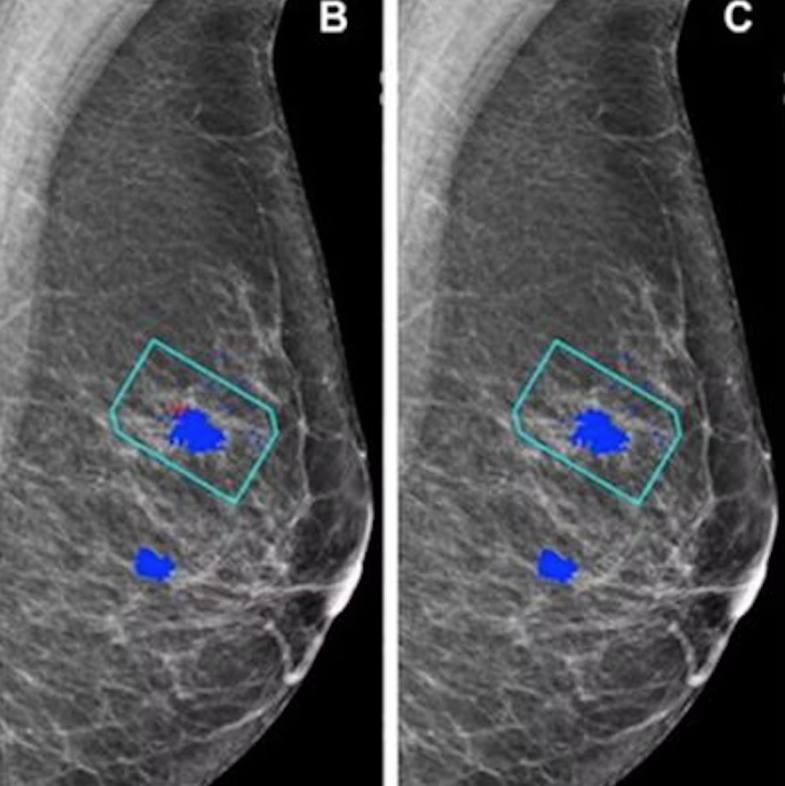

AI's impact on false-positive mammograms, breast cancer screening performance

Early adopter radiology departments have been testing imaging AI technology for reducing false-positive recall rates and radiologist workload.

In the U.S., only 0.5% of the approximately 10% of women recalled after an initial breast cancer screening actually receive a cancer diagnosis. LG's medical displays are designed to help reduce the risk of false positives.